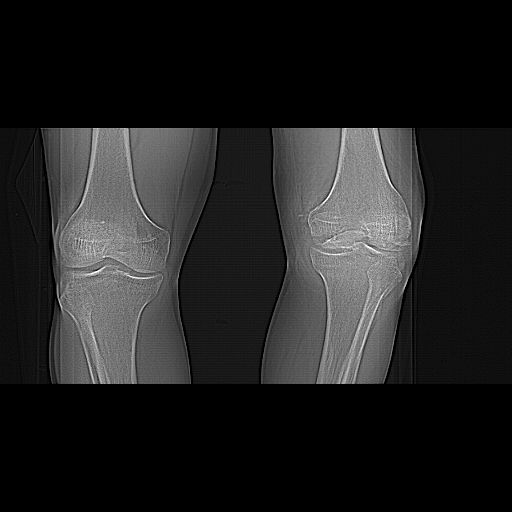

Before the CT and MRI era, we were treating the fractures with study of the Xrays alone. Such fractures with skeletal traction followed by non wtbearing mobilisation used to yield a fairly good range of movements. The CT gives a real ghastly picture of not so bad looking plain Xrays. I think this case needs traction to start with to correct the flexion deformity which probably will be achieved in 2 weeks time or less. We can then reassess the case with fresh Xrays. If possible one should try and fix the fragments to get some alignment. But the fixation should be stable enough to be able to mobilise the joint. Otherwise the traction can be continued for another 2 weeks to make the fracture sticky and then mobilise. We could get about 70 to 80* movements in spite of such communition. I am enclosing an Xray of a patient who is walking independantly and has 0 to 80* movemnts of the knee for the last one year

Cheers!

Dr V M Iyer